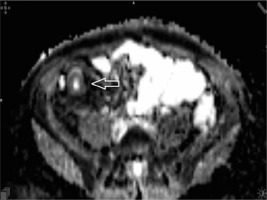

Figure 4

Apparent diffusion coefficient (value 1192) axial image demonstrating low signal intensity on the apparent diffusion map due to restricted mural diffusion of the terminal ileum (arrowhead)